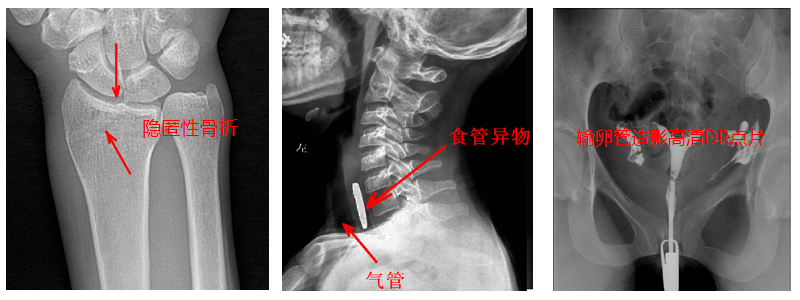

2.數(shù)字透視。適用于全身各部位透視(如胸透、腹透等),以及在透視下DR點片等;動態(tài)采集速度≥25幀/秒,應(yīng)用于消化科、泌尿科、婦科等。

4.數(shù)字造影。PLD5500B動態(tài)DR機適用于各種普通及特殊造影,如口服膽囊造影、靜脈膽道造影、T管造影、逆行胰膽管造影(ERCP)、靜脈腎盂造影(IVP)、子宮輸卵管造影、脊髓造影等,主要應(yīng)用于消化內(nèi)外科、泌尿外科、婦科、神經(jīng)內(nèi)外科等。

5.準確點片。在透視下準確找到病灶部位,這對于早發(fā)現(xiàn)隱匿性骨折有著不可替代的作用。更難能可貴的是,它可以在透視情況下進行整骨復位以及術(shù)后在透視下檢查。